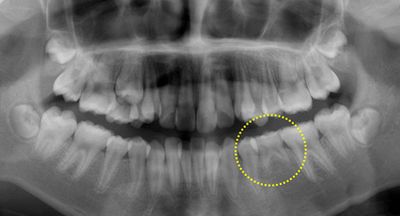

10歳の女の子、上下の前歯がガタガタで八重歯が気になるとのことで矯正相談に来られました。レントゲン撮影をしたところ、下あごの第二小臼歯が1本先天欠損しており、第二乳臼歯(黄色に丸囲い)が残存していることがわかりました。両隣りの永久歯と比較して咬み合わせの位置がずれておらず、根っこもしっかりしています。患者さん自身が非抜歯矯正を希望されているので、今回は乳歯をそのままの状態で抜歯せずに矯正治療を行うことになりました。上下顎ともに叢生量が大きい(ガタガタの度合いが大きい)ので、SH療法にて治療を計画しました。(小学生のレントゲン撮影をすると、10~20人に1人の割合で先天欠損が見つかります。)